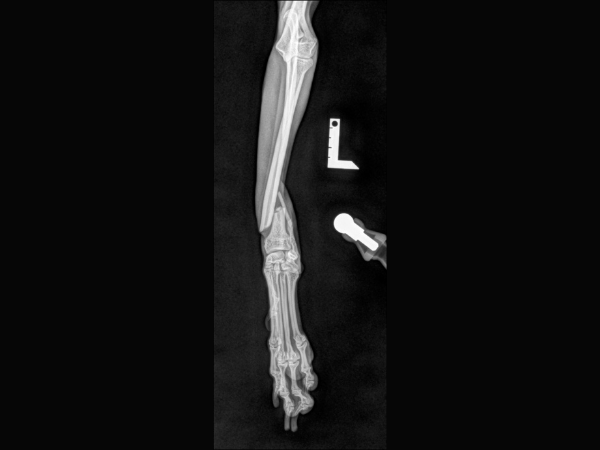

<術後のレントゲン>

インプラントによる内固定と海綿骨移植を行いました。

▼術後